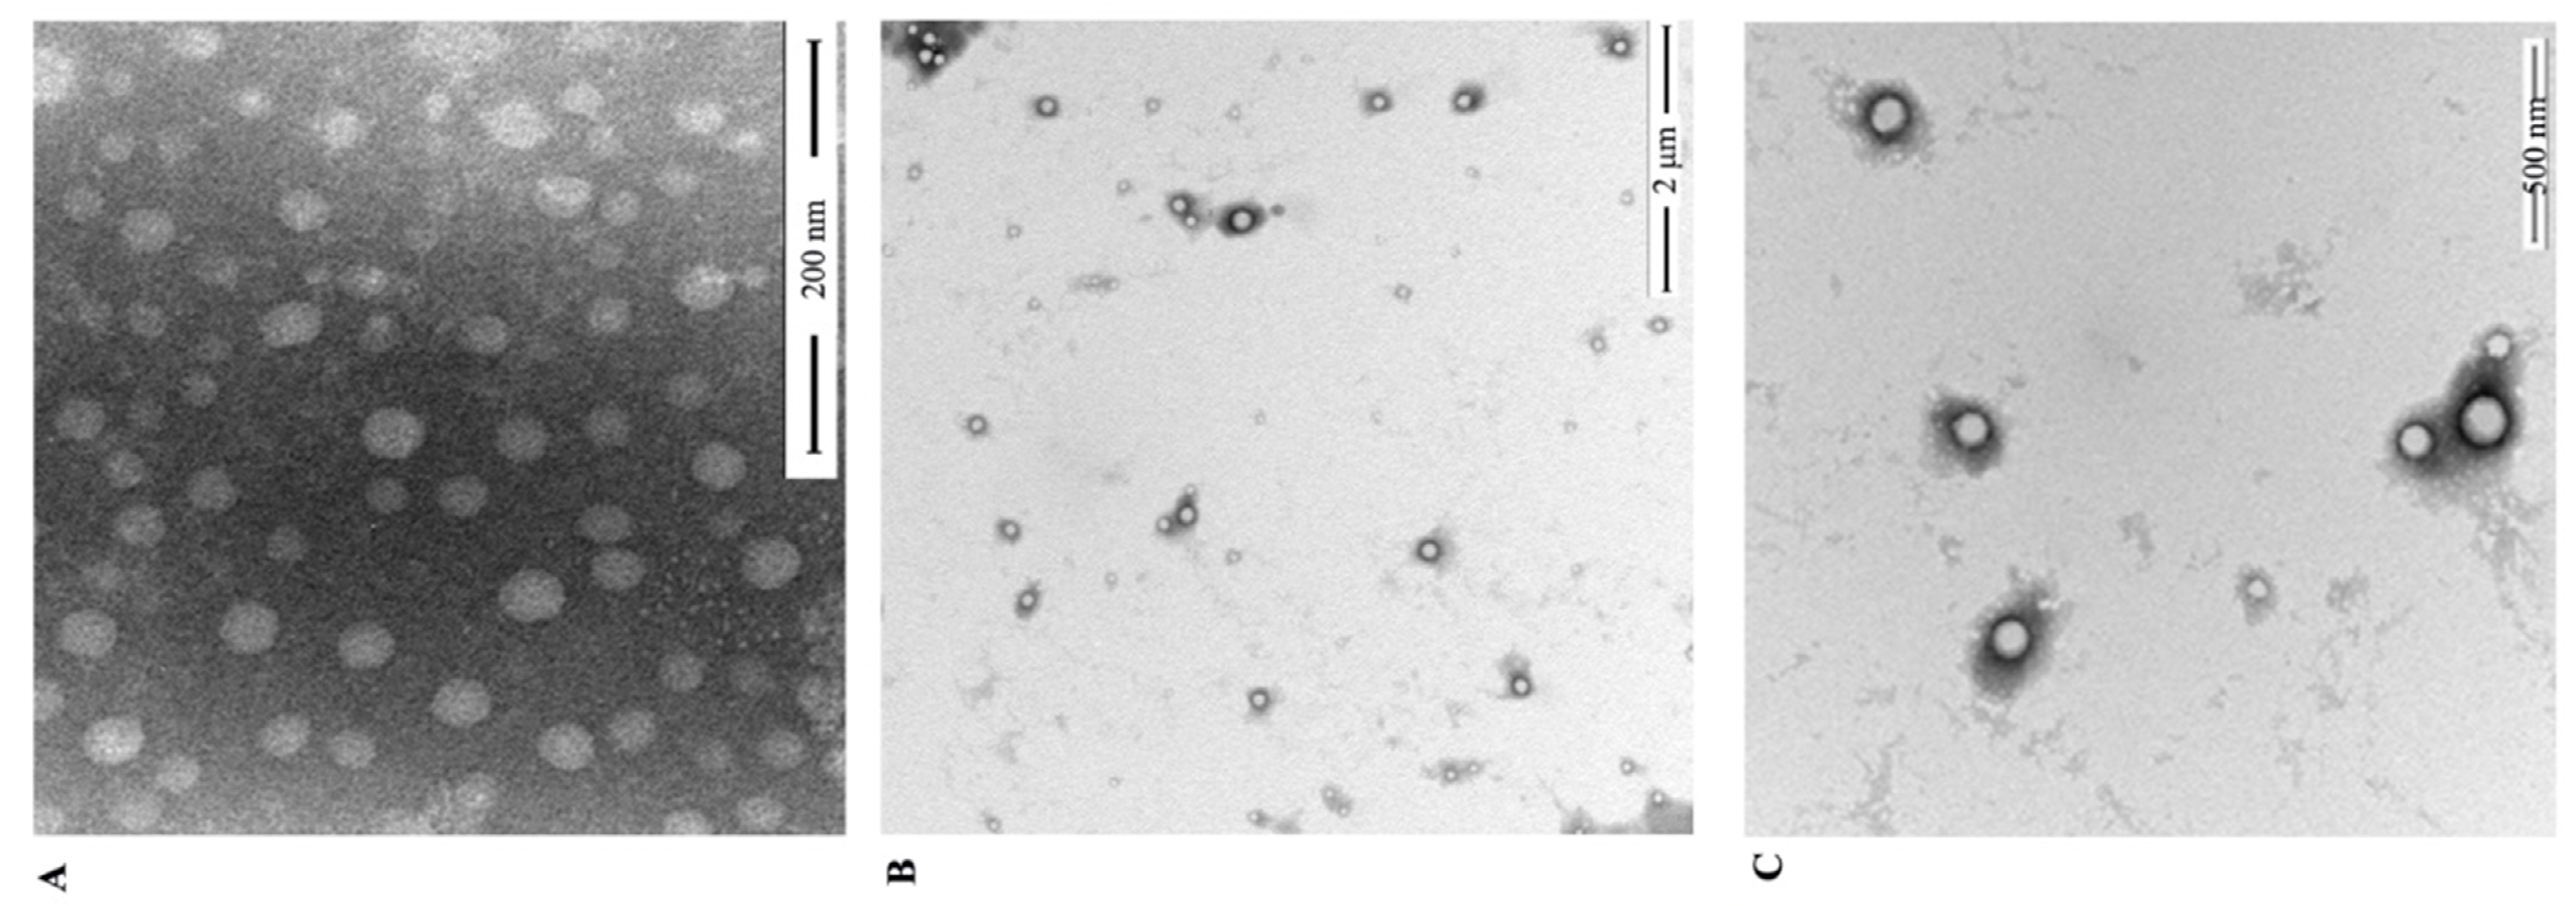

3.1. Preparation and Characterization of RES-PCAC-NPs